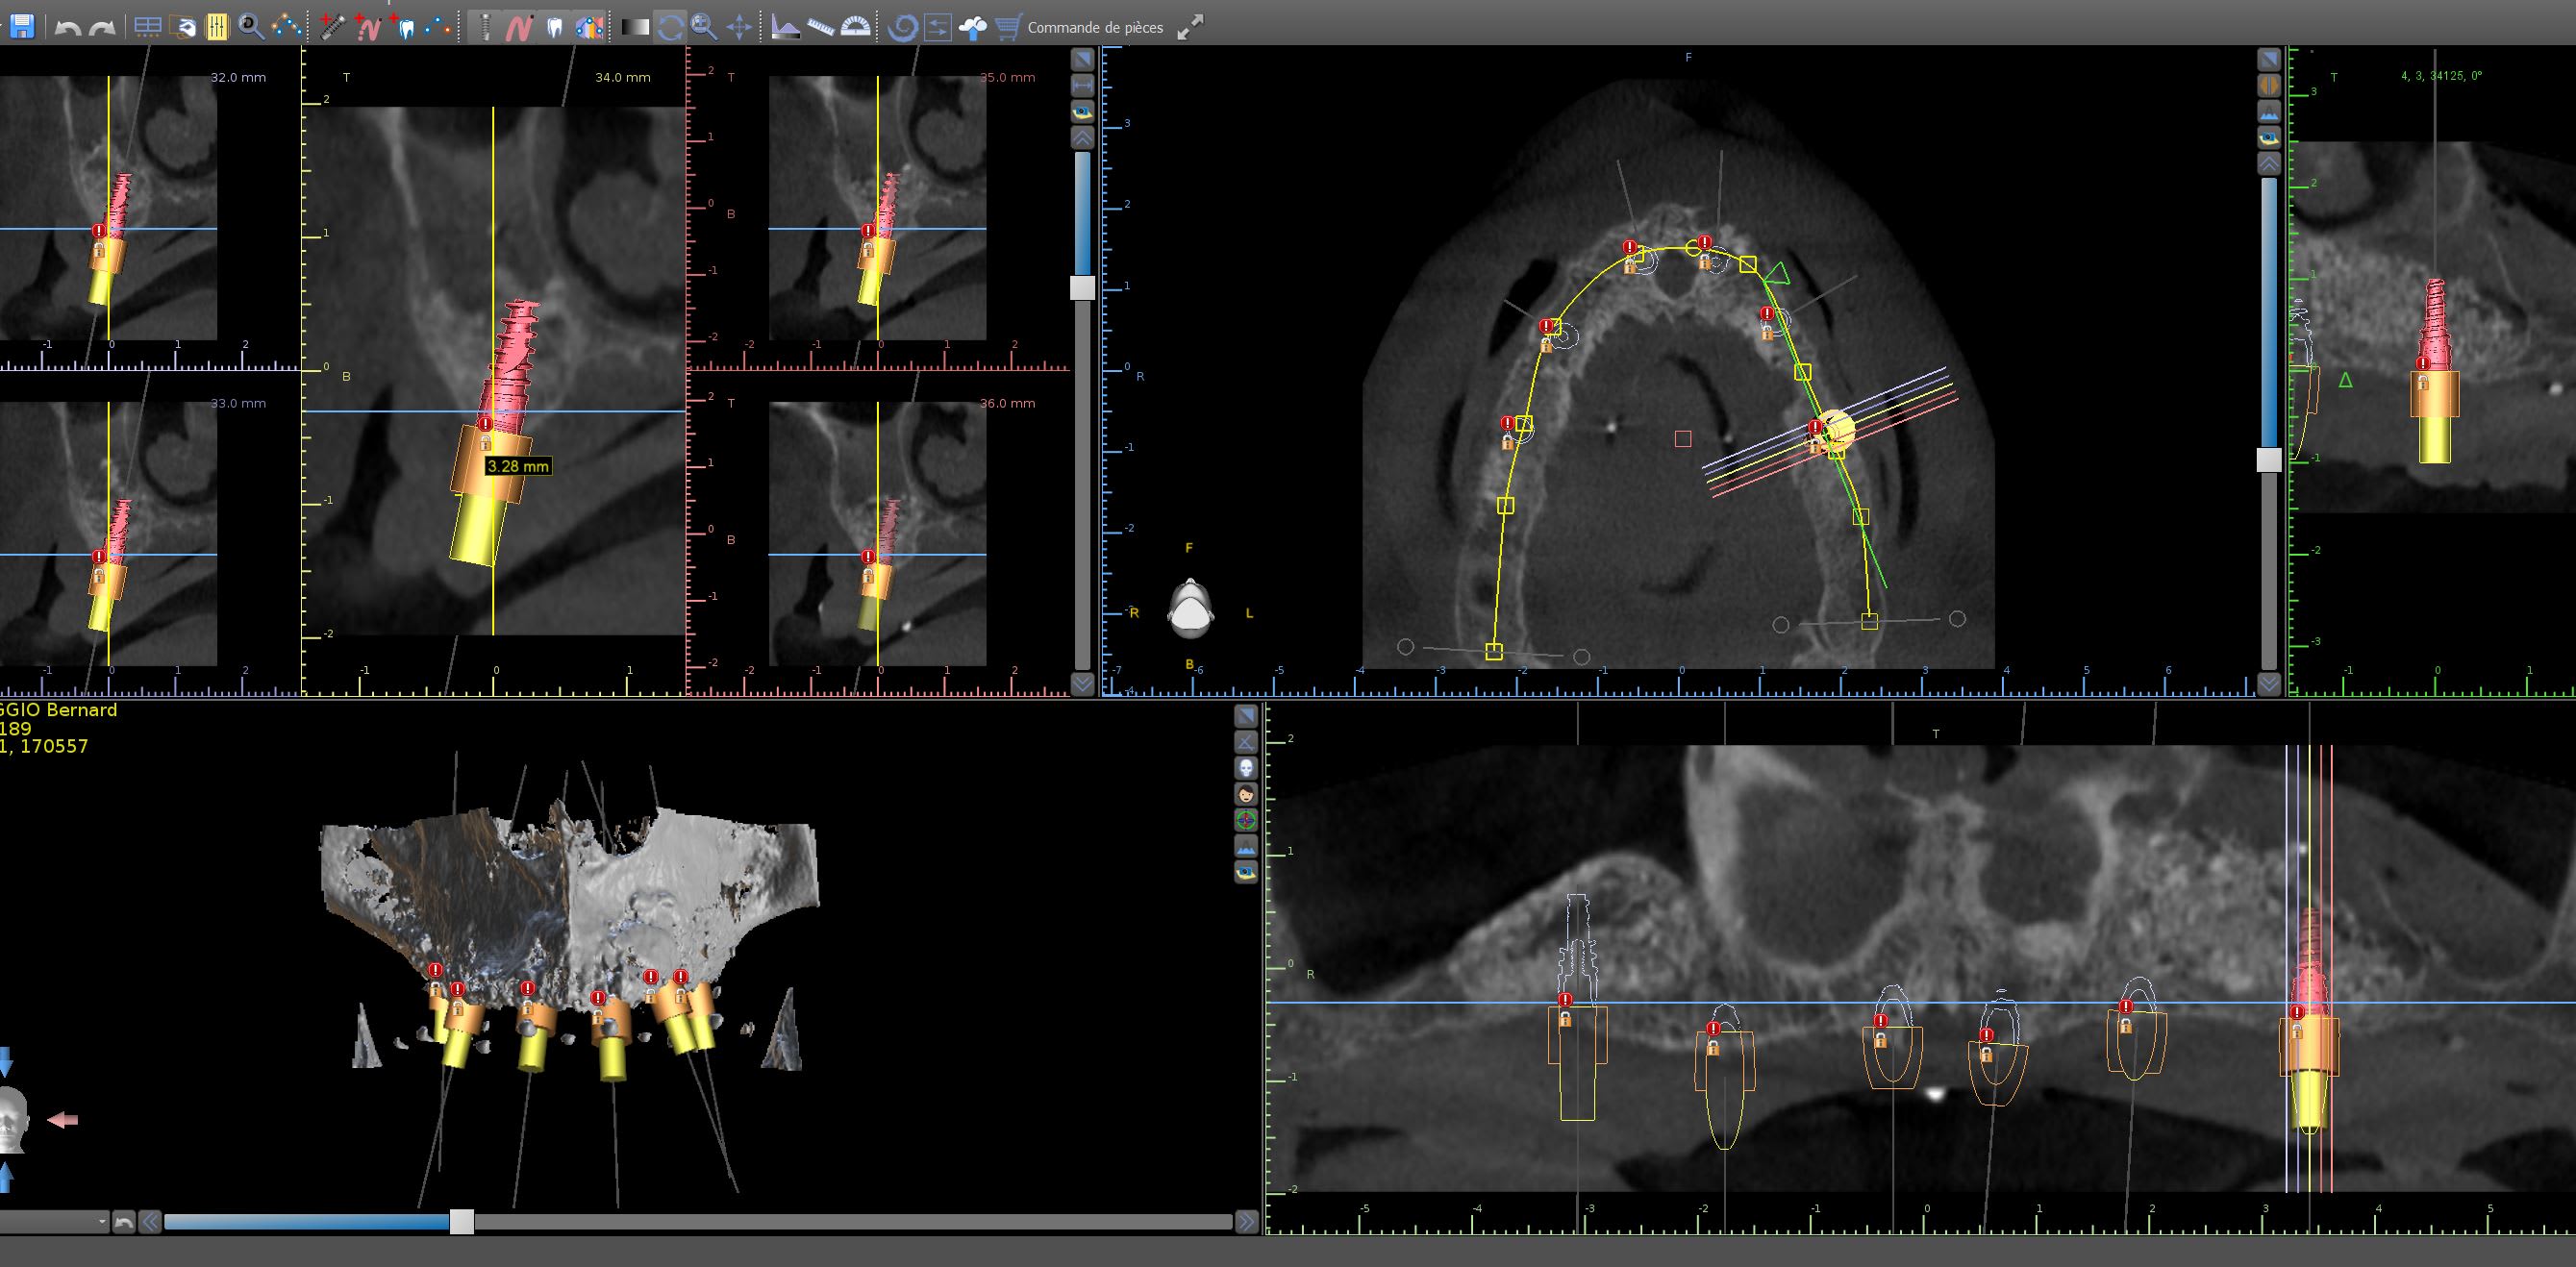

pour ceux qui ont franchi le pas ...

Capture ivkkug - Eugenol

Capture1 g1qpeb - Eugenol

Capture2 ctdd0n - Eugenol

Capture3 i5hyx6 - Eugenol

Capture4 g74a3u - Eugenol